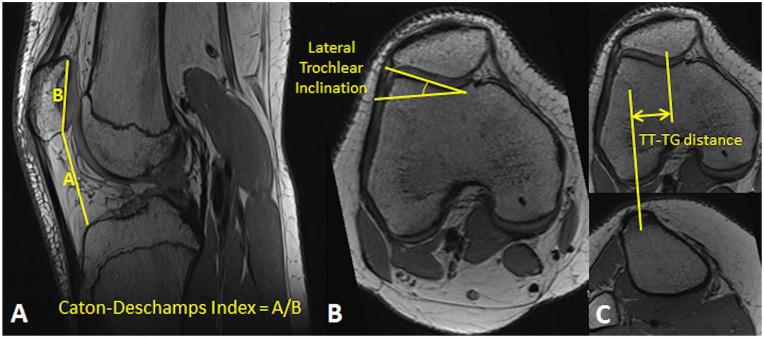

The study was performed to evaluate cartilage within the knee following a first-time patellar dislocation, using elevated MRI-based T1ρ relaxation times as an indicator of low proteoglycan concentration. The hypothesis is that MRI-based T1ρ relaxation times for patellofemoral and tibiofemoral cartilage are significantly longer for knees being treated for patellar dislocation than for healthy control knees.

Twenty-one subjects being treated for a first-time, unilateral dislocation of the patella and 16 healthy controls participated in MRI-based T1ρ relaxation time mapping. Mean relaxation times were quantified for patellofemoral and tibiofemoral regions for injured knees, the contralateral knees, and healthy controls. T1ρ values for each region were compared between the 3 groups with generalized estimating equations. Linear regressions were also performed to correlate T1ρ relaxation times with time from injury.

The knees with a disloction had longer T1ρ relaxation times than the contralateral knees and control group at the medial patella and longer relaxation times than the control group at the lateral tibia ( < 0.05). T1ρ relaxation times at the medial patella also decreased with time from injury (r = 0.21, = 0.037).

Compositional changes to cartilage on the medial patella are related to traumatic impact during a dislocation. Potential exists for cartilage properties at the medial patella to improve with time. Cartilage degradation at the lateral tibia is not directly related to traumatic impact. The current baseline data are a starting point to characterize the pathway from a first-time dislocation to progressive cartilage degradation and osteoarthritis.